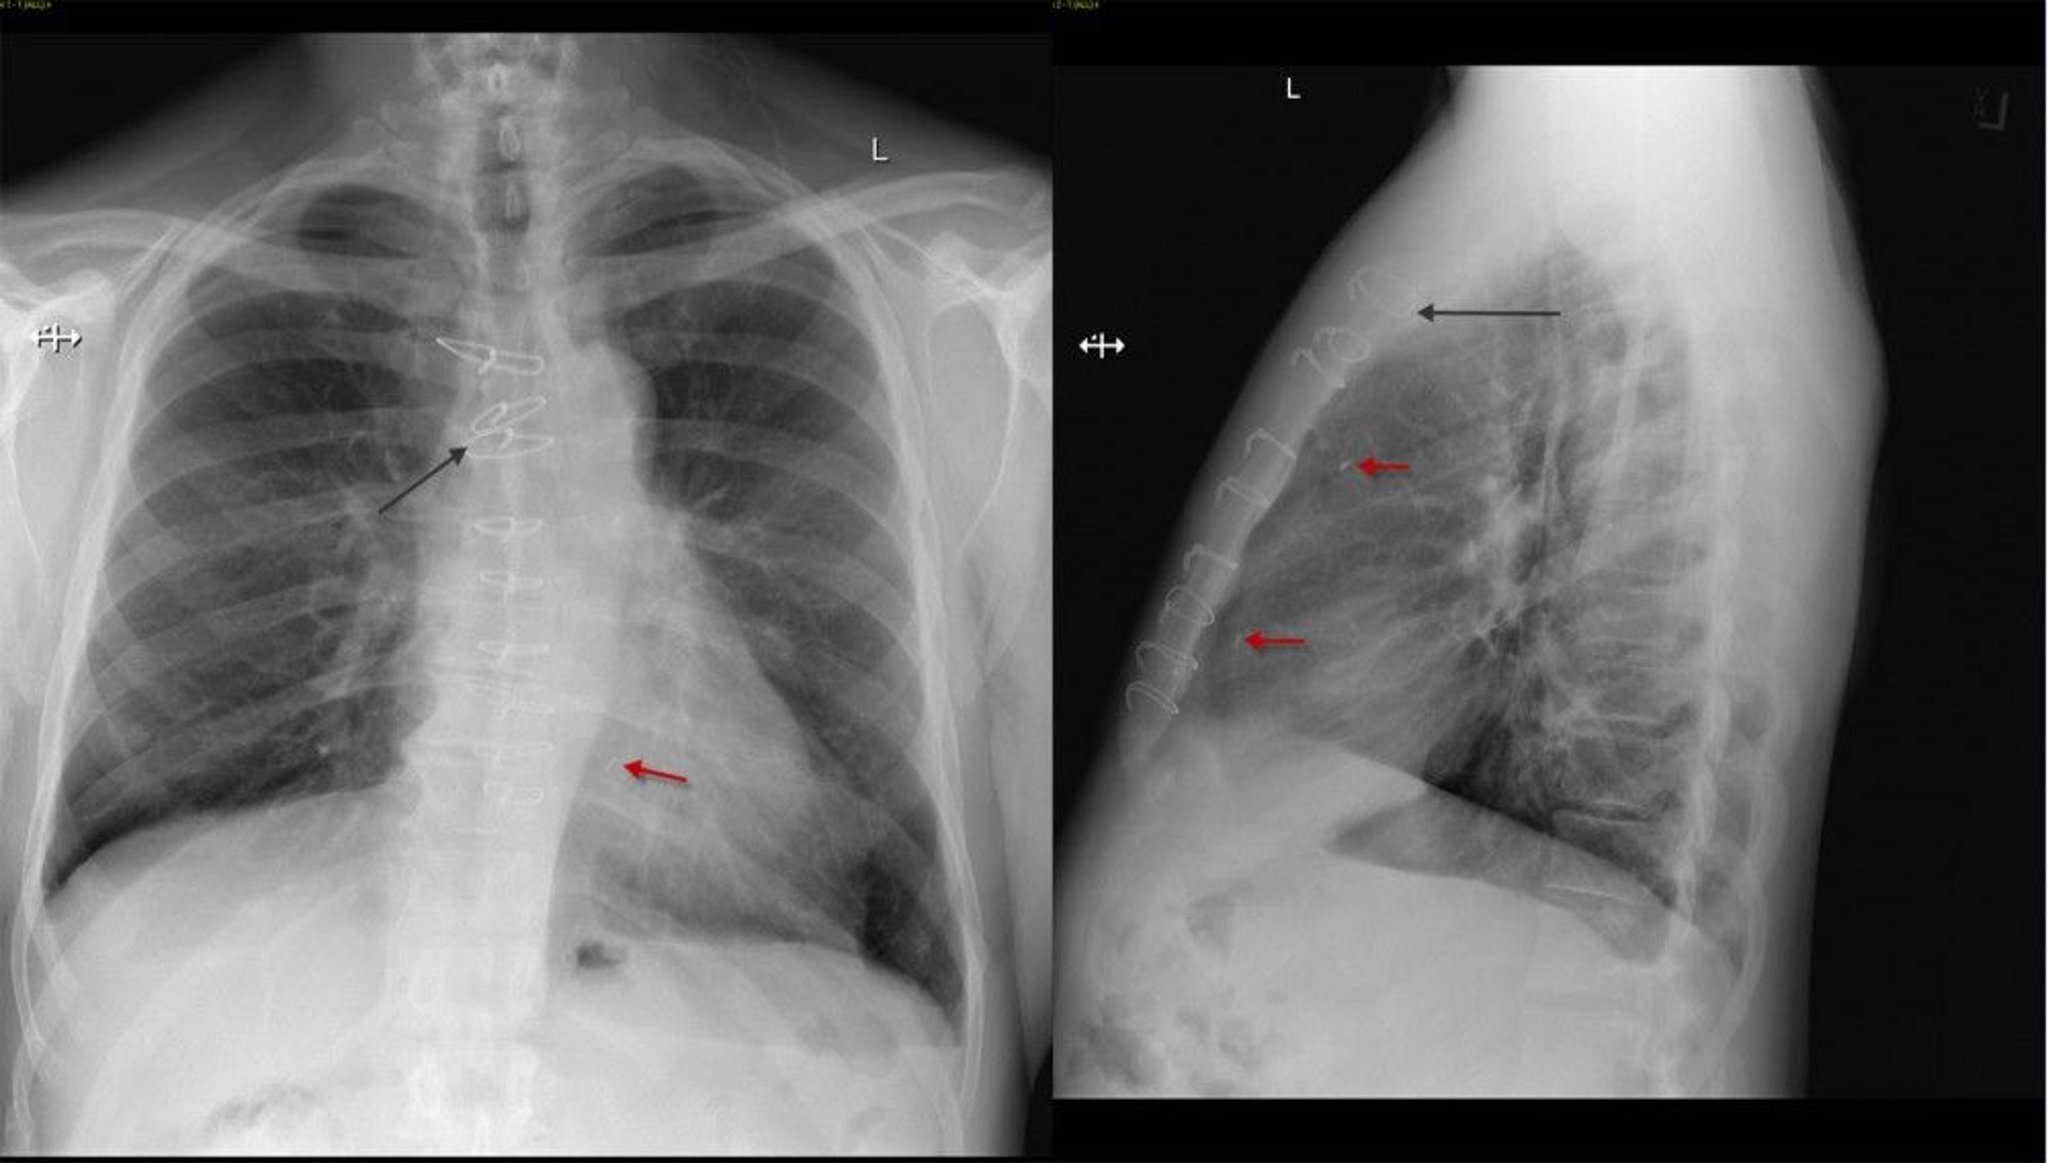

Radiografía de tórax frontal y lateral de un paciente después de una cirugía de derivación de la arteria coronaria que muestra suturas esternales (flecha negra) y clips quirúrgicos (flecha roja).